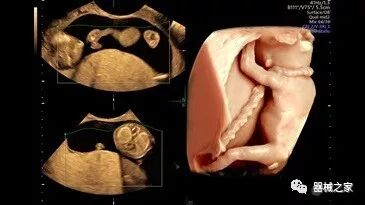

在RSNA 2018上发布的新成像被开发用于解决胎儿心脏和脑部成像问题。由于体积小且心率极快,因此难以进行详细的胎儿心脏评估。在18周时,胎儿的心脏大小与橄榄相当,每分钟跳动约150次。此外,结构本身非常复杂,婴儿不断运动,它始终是一个移动的目标。成像很重要,因为先天性心脏缺陷会影响全球每110个婴儿中的一个。

GE Healthcare用于胎儿超声的胎儿心脏和血管分析软件,在Voluson E10上提供,有助于在不到三分钟的时间内评估胎儿的心脏形状,大小和收缩性。称为辐射流的功能以三维视图显示血流。它还可以帮助显示缓慢流动的血液,例如神经血管循环。

2018年发布的另一个例子是飞利浦的TrueVue,它提供照片般逼真的渲染,并能够在三维超声图像上改变光源的位置。它允许用户改变照明条件以提高对比度。可以移动光源以改变阴影并增加更多深度感知。还可以推动光源穿过组织以对解剖结构进行背光。